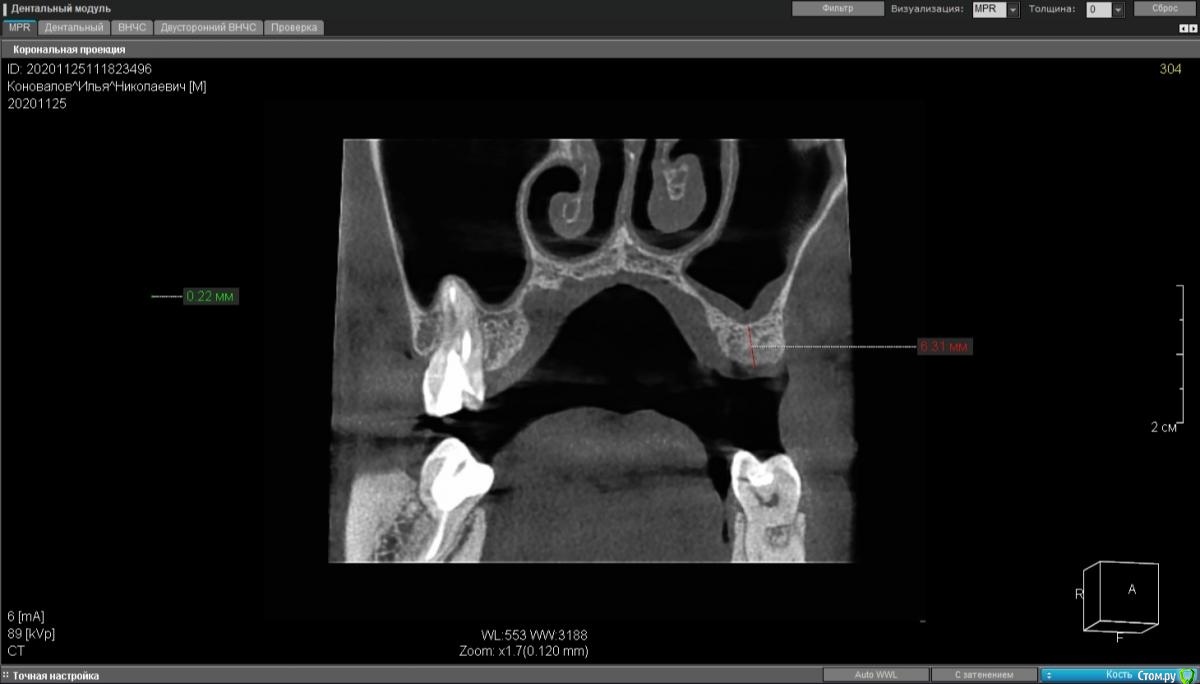

moises Опубликовано 30 ноября, 2020 Поделиться Опубликовано 30 ноября, 2020 Добрый день,коллеги.3 месяца назад удалены 25,26.Планируется установка 2х имплантатов .Если в области 15 можно было пойти с закрытым синуслифтингом, то в области 16 кости 3мм.Нужна помощь в тактике лечения.?Идти на ОСЛ в области 2х зубов и отсроченно имплантаты ? И можно ли с такой утолщенной слизистой его производить?Спасибо!P.S.Закрытые синусы делаю,открытые -делал только на фантомах и препаратах. Ссылка на комментарий

Александр07 Опубликовано 26 декабря, 2020 Поделиться Опубликовано 26 декабря, 2020 коллеги простите за офтопа если соустье плохо проходимо или обтурировано или не прослеживается, но жалоб на заложенность или явления гайморита нет и по снимку нет воспалений, что делаете, какая подготовка к операции, какие рекомендации?что искать на КТ как смотрите соустье, на что обращать внимание?Соустье на кт видно обычно хорошо в верхнем отделе пазухи, если закрыто или ещё что или к Лору или назначить назонекс на месяц например и затем повторить кт, но если утолщение не большое и вся пазуха чистая то с соустье скорее всего все в порядке 1 Ссылка на комментарий